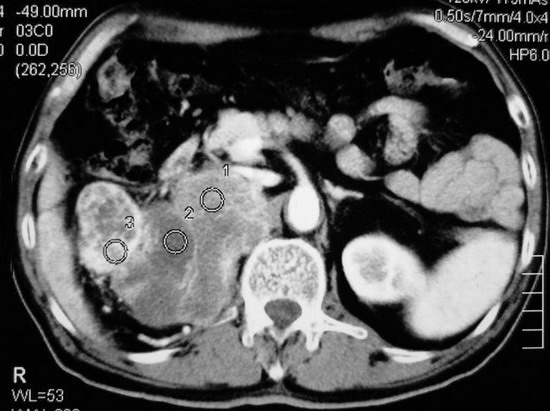

以下是引用杀毒软件在2008-11-17 19:15:00的发言:[br]考虑------右肾癌合并肾静脉---同侧肾上腺受侵可能性大

以下是引用zjzjr在2008-11-17 20:45:00的发言:[br]考虑------右肾癌合并肾静脉---同侧肾上腺受侵可能性大及腹膜后淋巴结转移.